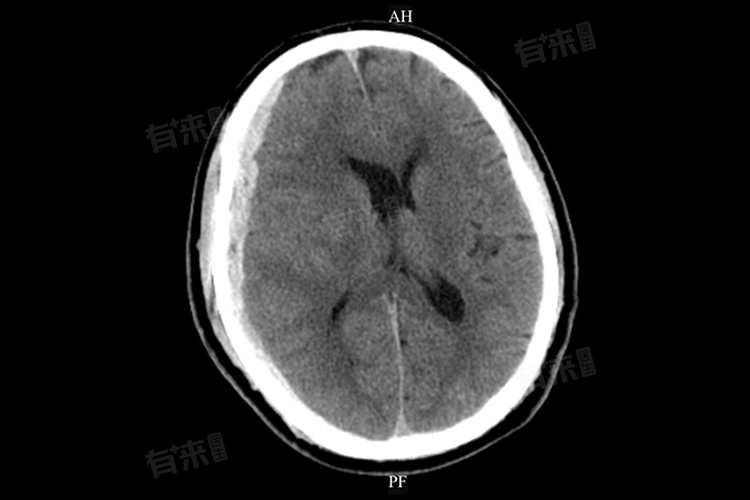

- 医生诊断硬膜下出血,主要依靠头颅CT检查,可清晰显示颅骨内板下新月形高密度影(急性)、等密度影(亚急性)或低密度影(慢性),MRI检查对发现等密度血肿及了解血肿演变过程更具优势。